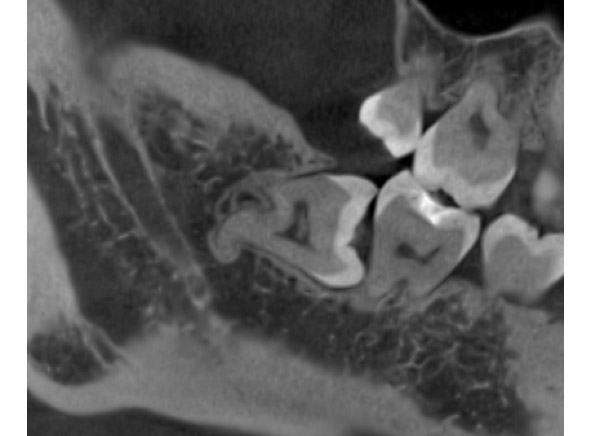

☆本院特別巨資增設 ”千萬級3D AI透視電腦斷層”,並配合“成骨膠原蛋白”施作 (上述兩項目前健保無給付),讓您遠離神經傷害、口鼻竇(炎)相通...等併發症,除健保之外,難免會有避免併發症風險的自費項目,網路上經常會有看到智齒拔完後唇麻、舌麻、口鼻竇相通等併發症,在本院嚴格自我要求下,此類併發症在本院幾乎趨近於零。

外面拔時易斷裂於骨頭內而難以取出